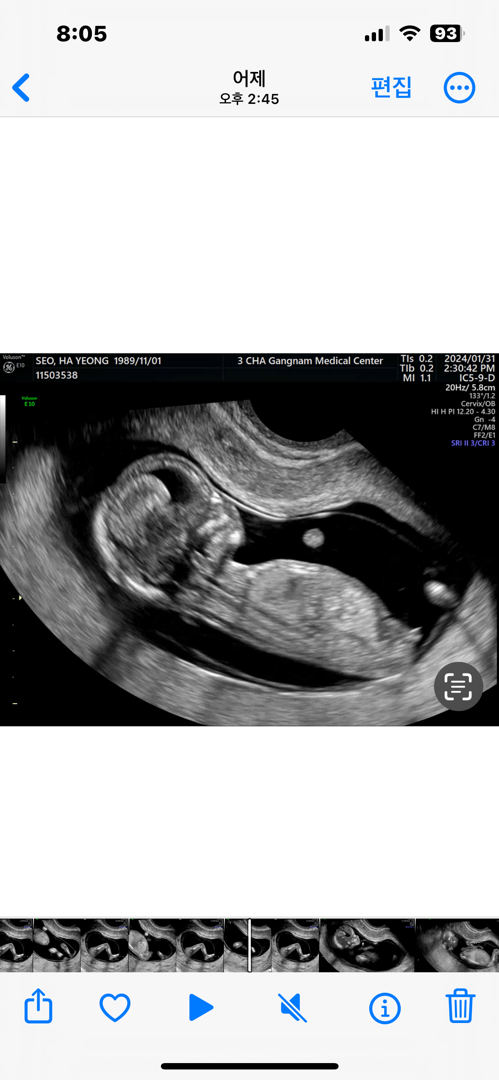

12주4일! 아들일까요?ㅎㅎ

의견부탁드려용ㅋㅋ

아들같아요ㅎㅎ

아들같은 느낌!!? ㅎㅎ 선생님은 힌트안주시던가요? ㅎㅎ